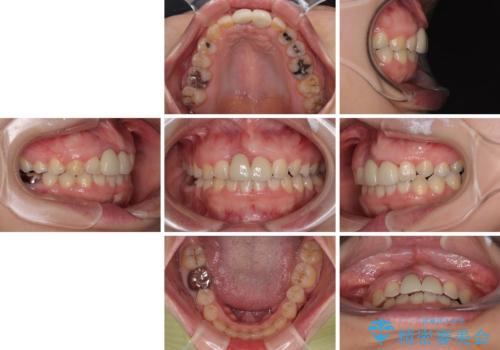

前歯のデコボコをワイヤー矯正で綺麗に 保険診療の前歯クラウンもセラミッククラウンで自然に

前歯のクラウンは変色が顕著なため、矯正治療後にオールセラミッククラウンによる補綴治療を行うこととしました。

前歯のクラウンは、歯肉内深くに削り込まれており、歯肉の炎症が継続していたため、矯正治療後に歯周外科処置を行い、歯肉の腫れを改善させました。